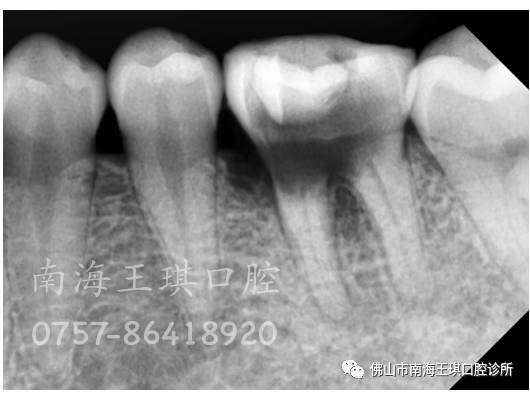

片子显示底穿了,牙槽骨也吸收很多了。根尖周围也有阴影的。

龋洞是细菌的温床。一个长年累月没有封住的洞,更加滋生了很多细菌,把髓底都“吃”穿了,并且,整个牙体,也完全成了个空壳。只能拔掉种牙了。

还不好拔。牙挺一碰,就碎了好多片,可以明确的看到底部烂得相当严重。

分根来拔,牙槽骨都有明显的吸收。